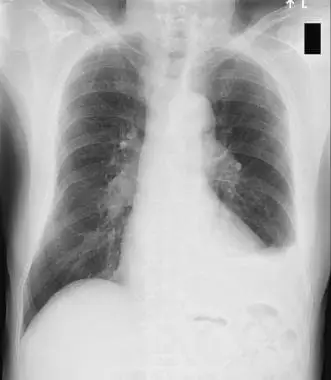

그렇게 정신줄을 간신히 붙잡은 채 일을 해나가고 있을 무렵 옆에 계신 교수님께서 아까 환자분의 X-ray라며 사진을 하나 보여주셨다.

원래 같으면 새까맣게 보여야 할 왼쪽 폐가 새하얗게 보이고, 뾰족해야 할 폐의 끝부분이 뭉툭하게 보이고 있었다.

왼쪽 흉강에 가득 찬 흉수

사진 소견만으로도 숨쉬기가 얼마나 힘들 셨을지 짐작이 되는 X-ray를 본 뒤 환자분을 호흡기 내과에 연결하였고 담당 선생님께서 내려오셔서 환자분에게 현 상태와 당장 어떤 치료가 필요한지 설명을 해주셨다.